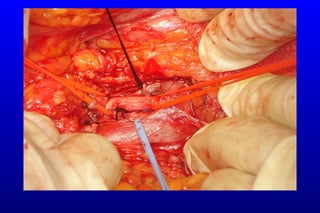

Cerrahi embolektomi ± rezeksiyon

Non viable dokuların rezeksiyonu + anastomoz / stoma